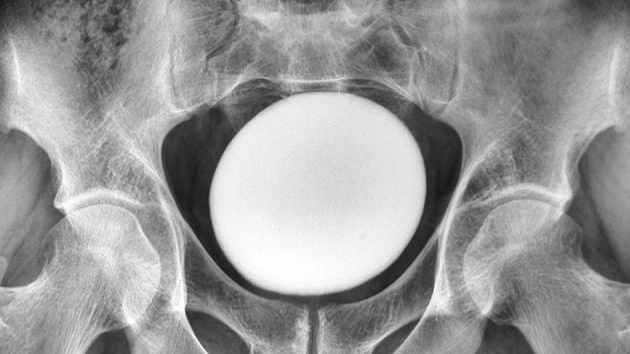

Diagnostic dilemma: Giant 'stone' in a man's bladder looked like an ostrich egg

The dense mass wasn't attached to the pelvic area or abdominal wall, and an ultrasound scan revealed that it was an egg-shaped object about 4.3 inches (11 centimeters) in diameter, according to a report of the man's case.

The extracted stone weighed 1.8 pounds (826 grams) and measured about 5 inches (13 cm) long, 4 inches (10 cm) wide and 3 inches (8 cm) tall.